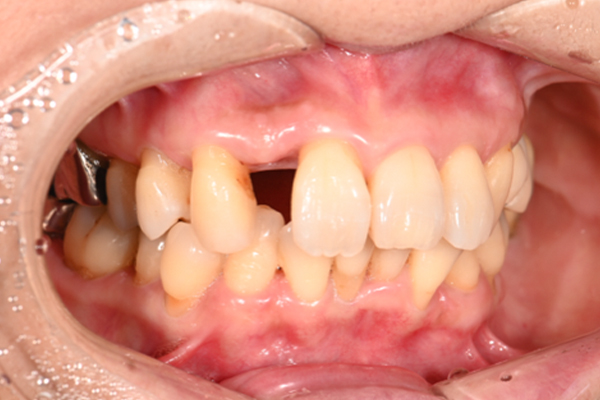

| 主訴 | 奥歯で噛めない、顎が痛い |

|---|---|

| 治療内容 | 奥歯のインプラント治療、前歯・奥歯の被せ物治療 |

| 治療期間 | 6ヶ月 |

| 治療費 | 350万円 |

| 治療リスク | 被せ物をつけた初期の段階で歯がしみることがある(時間とともに改善する) インプラント治療後に3日程度痛みと腫れを伴うことがある |